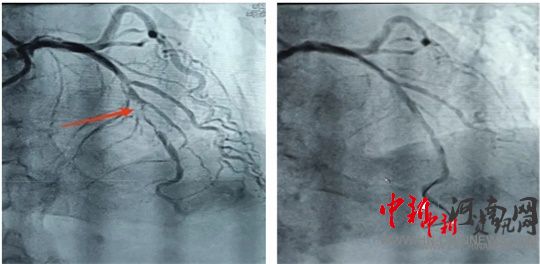

術(shù)前 術(shù)后

造影結(jié)果顯示,前降支中段次全閉塞。經(jīng)過充分預(yù)處理病變后,應(yīng)用一枚藥物球囊進(jìn)行治療。隨后,患者癥狀明顯緩解,生命體征恢復(fù)平穩(wěn),送入重癥監(jiān)護(hù)室進(jìn)行過渡觀察。